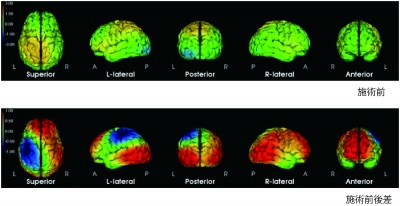

REFLE(リフレ)は脳神経外科医との共同研究を実施。100名を超える認知症患者にリフレクソロジーを行った結果、興奮や怒りが収まり、鮮明に脳に変化が表れたことが実証されました。(図:認知症患者にリフレクソロジー施術をした際の脳波解析) また、介護老人保健施設のご協力をいただき、利用者の方の施術後の変化を、看護師・介護士の皆様に客観的に評価をしていただいたところ、リフレクソロジーの施術がプラスの効果をもたらすことが実証されました。 ▼詳細はコチラ▼ https://www.refle.co.jp/medical/